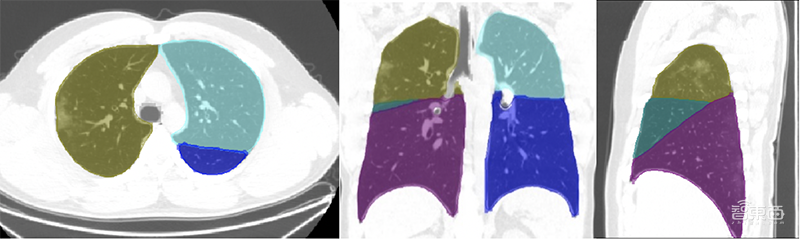

2)自动分割系统:结合深度学习和传统方法,通过解剖结构分割、肺部炎性病灶分割、肺结节自动分割等方式,更快提取病灶并进行更精准的定量分析。

GE医疗推新冠病毒AI平台!解读背后的硬核技术▲分割肺叶